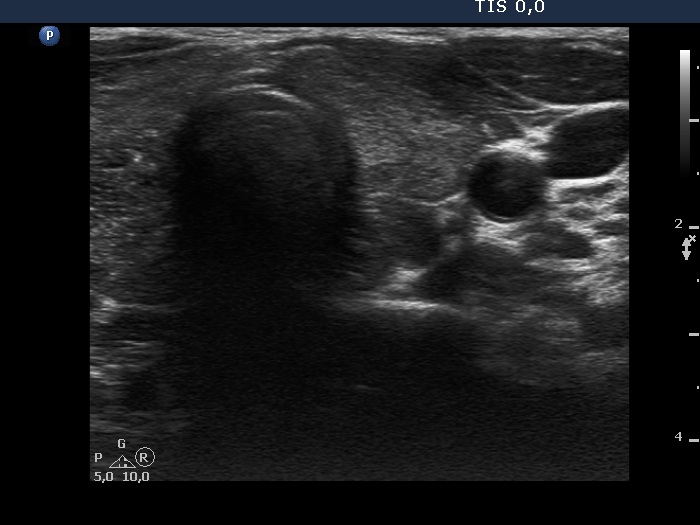

100 consecutive cases of papillary cancer - case 088 (ultrasonographic picture 8)

Left lobe, transverse scan. This lobe has hypoechoic areas.